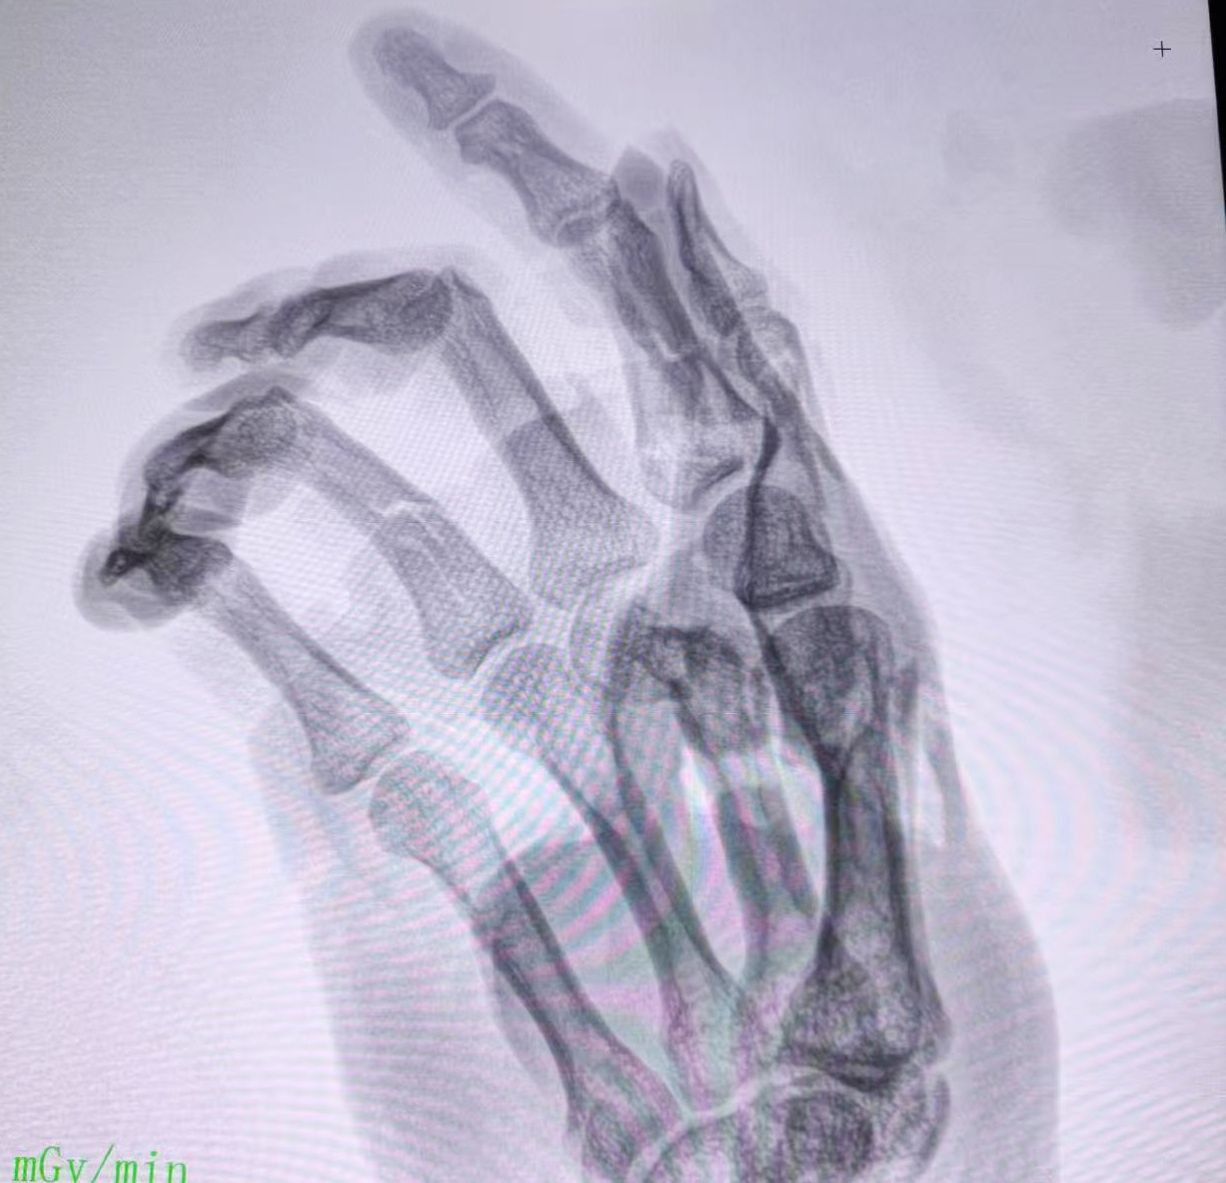

医护消防手术室联手上演“虎口夺手”

5月30日晚,珠江医院多科室与消防部门协作,为一名因绞肉机挤压跤轧伤的29岁男子展开抢救,患者手术成功,后续需进行系统康复训练,回归正常生活。阿彬(化名)右上肢被卷入运转的绞肉机,右手与冰冷机器死死“锁”在一起,被120救护车火速送往珠江医院急诊科。急诊科医护人员争分夺秒建立静脉通路、输液抗休克,稳定了患者生命体征。“必须立即手术保肢。”珠江医院创伤骨科副主任医师…